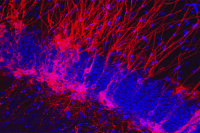

In the hippocampus, the dentate gyrus—which uses pattern separation to form new memories—is one of two areas of the brain where neurogenesis takes place. Although the extent of adult neurogenesis in humans, as well as its role in stress responses, is controversial, Hen and his team think that a reduction of hippocampal neurogenesis contributes to the impaired pattern separation underlying anxiety disorders. Structural MRI studies of the brains of PTSD patients have shown decreased volume of the dentate gyrus. Two potential approaches to improving pattern separation are to increase the number of adult-generated neurons or to modify the mature neurons so they are better able to process information.